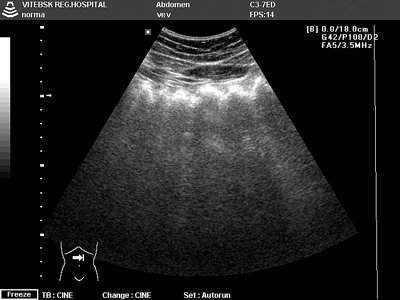

Опухоль кишечника на узи

Опухоль кишечника на узи 115 фото